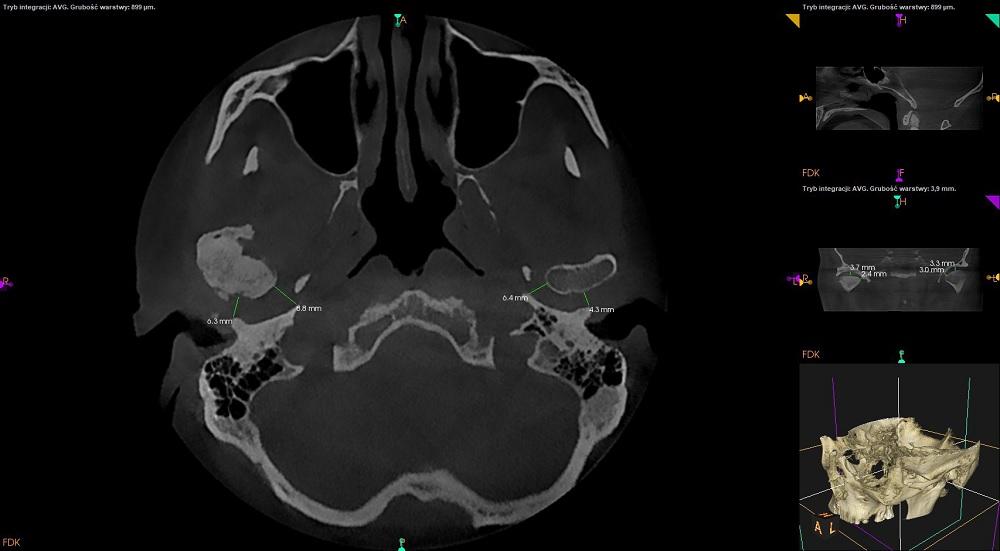

CBCT stawów skroniowo – żuchwowych w zwarciu.

Uwidoczniono zaawansowane zmiany zwyrodnieniowe w obrębie prawego stawu skroniowo – żuchwowego z objawami:

-szpara stawowa zwężona,

-występuje sklerotyzacja podchrzęstna powierzchni stawowych,

-powierzchnie stawowe spłaszczone,

-na przedniej powierzchni prawej głowy żuchwy osteofit, czyli wyrośla kostne.

Znaczna sklerotyzacja wyrostka kłykciowego wraz z przebudową zzś jest dobrze widoczna na przekroju strzałkowym.